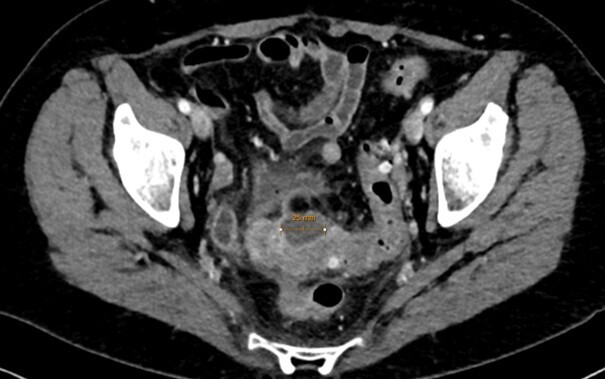

Le scanner abdomino-pelvien avec injection intra-veineuse de produit de contraste en l’absence de contre-indication (fig. 1) est recommandé en première intention pour le diagnostic et la recherche des complications ;1 l’IRM abdominale est une bonne alternative, notamment en cas d’allergie sévère au produit de contraste ou pour les femmes enceintes. L’opacification digestive basse n’est plus indiquée dans la prise en charge initiale. L’imagerie peut être discutée et parfois omise chez des patients aux multiples récidives et en l’absence de critères de gravité (péritonisme clinique, syndrome inflammatoire marqué…).

Les diverticulites abcédées sont également traitées par antibiothérapie, couplée à un drainage radiologique pour les collections de grande taille (plus de 4 cm).